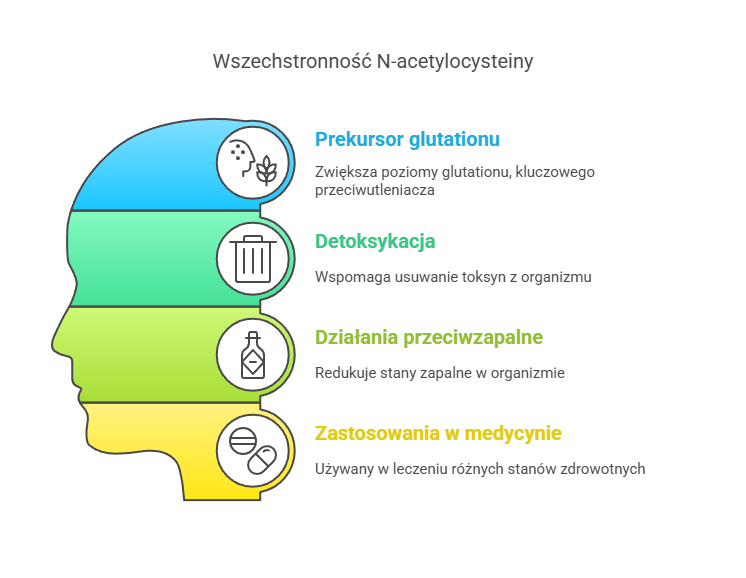

Podstawowe informacje o NAC pokazują, że jest to związek o niezwykłej wszechstronności. Działa jako prekursor glutationu – najważniejszego przeciwutleniacza w naszym organizmie, wspomaga procesy detoksykacyjne, wykazuje działanie przeciwzapalne i wpływa korzystnie na liczne układy organizmu – od oddechowego po nerwowy.